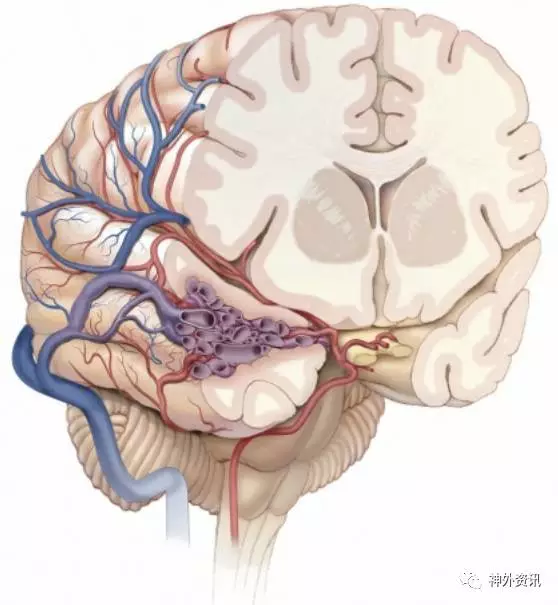

图1. MCA上干分支成为绝大多数侧裂和颞叶侧面AVMs的供血动脉(图谱来自于AL Rhoton, Jr)

颞叶的供血动脉既有前循环来源的(通过外侧裂内的大脑中动脉下干供血),也有后循环来源的(通过大脑脚池和环池的大脑后动脉分支供血)。

总体来说,颞叶侧裂区及外侧面的血供主要来于自大脑中动脉分支;而颞叶下部及底面主要由大脑后动脉分支供血。颞叶前内侧组织,包括杏仁体和海马,血供来自于脉络膜前动脉、丘脑前穿通支(后交通动脉的分支)和大脑后动脉穿通支。颞叶后内侧的血供来自大脑后动脉的分支。

颞叶动静脉畸形病变位置不同,大脑中动脉和大脑后动脉的供血情况也不同;因此,术前每一例型AVMs都需要单独研究。